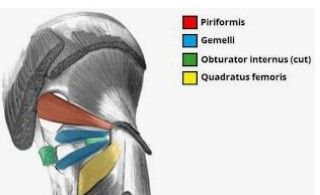

What is the origin and Insertion of quadratus femoris?

Origin

Ischial tuberosity

Insertion

Intertrochanteric crest of femur